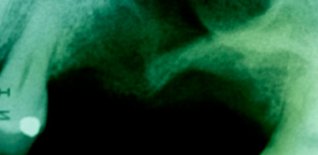

Grande rialzo del seno mascellare

Perdita di elementi dentari postero-superiori di destra, con assenza di osso per poter posizionare impianti osteo-integrati.

Si rigenera l'osso necessario attraverso l'intervento di GRANDE RIALZO DEL SENO MASCELLARE.

A rigenerazione ossea stabilizzata si procede all'inserzione degli impianti e alle fasi protesiche definitive.